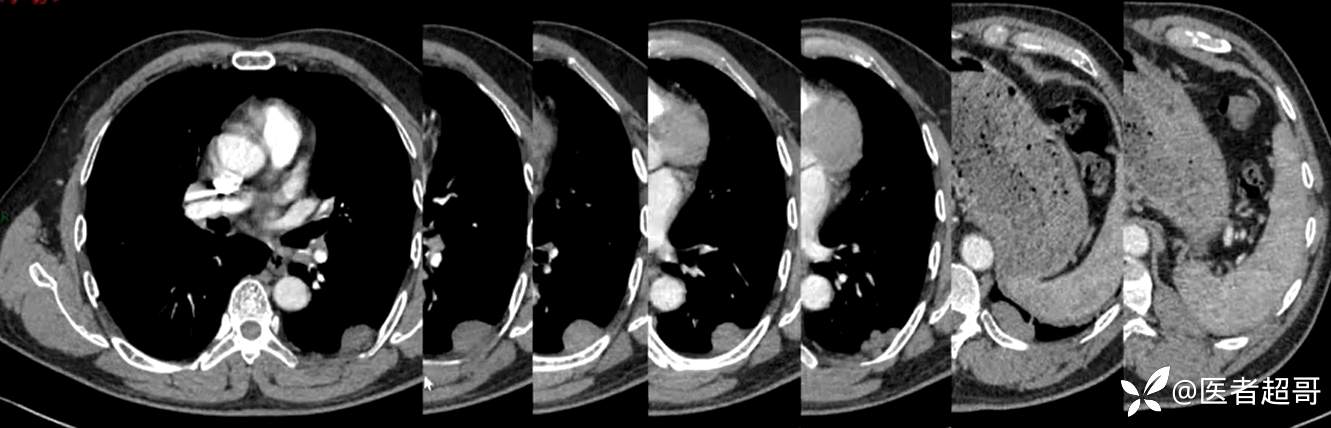

现病史:患者5月前因咳嗽、咳痰于当地医院就诊,完善胸部CT提示:胸膜多发占位,期间患者无胸闷、气紧、咳嗽、咳痰、心慌等不适,患者于我院门诊行胸部CT提示:左下胸膜增厚并见多个软组织密度结节影局限性凸起,较大者大小约3.5x2.2cm,增强扫描呈持续性轻度强化,考虑肿瘤性病变可能性大;门诊遂以:胸膜肿瘤收入我科。